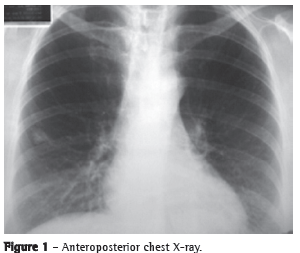

A 57-year-old Caucasian female (born in the city of Juiz de Fora, in the state of Minas Gerais, married, and a retired teacher) was referred to the SPCT-HMS-JF because the X-ray (Figure 1) prior to cholecystectomy revealed a nodule (of unknown stability and with irregular borders) in the right pleural cavity. The patient, who was totally asymptomatic, was a smoker (20 pack-years) and had a family history of cutaneous amyloidosis.

The present case was one of nodular pulmonary amyloidosis, which happened to be diagnosed through tests performed prior to cholecystectomy. The clinical and radiological evidence indicated a nodule of neoplastic origin since the radiological finding revealed a nodule with irregular borders, and the patient had a history of smoking. Consequently, we chose to perform an exploratory thoracotomy that allowed the correct diagnosis, and that, in case of malignancy, would make it possible to perform a potentially curative procedure. Therefore, the X-ray finding of a nodule with irregular borders in the right pleural cavity can lead to the inclusion of pulmonary amyloidosis in the radiological differential diagnosis.